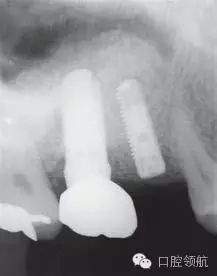

患者10年前,在外院于( 左上第六顆牙)區(qū)行上頜竇底提升術(shù)同期植入種植體,經(jīng)過10年上頜竇內(nèi)生成骨完全吸收消失了(圖1)?;颊叽舜蝸碓菏且?yàn)猷徰? 左上第五顆牙) 不能保存,希望行種植修復(fù)治療。

圖1 術(shù)前牙片。由于上頜竇底黏膜提升植骨術(shù)而在上頜竇內(nèi)生成的骨已完全消失。